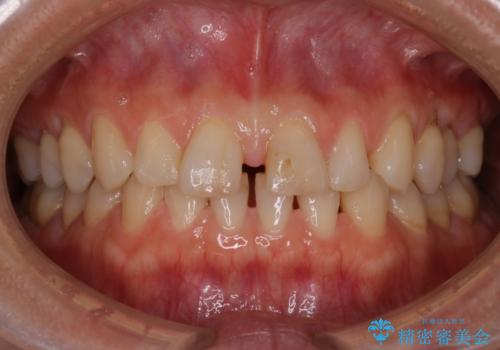

【インビザライン】前歯をきれいな歯並びにしたい

- 前歯の叢生を主訴に来院されました。このケースは抜歯をせずにIPRにてスペースを確保し、並べる計画をたてました。

きちんと使用時間を守って使用していただいたことで短い期間で治療が終了しました。